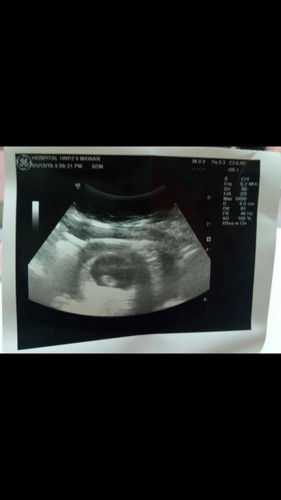

Alhamdulillah.. 8 weeks 5 days..

1/12/2019 ( Ahad).. Jam 4 ptg.. Admit wad tghari.. Syukur alhamdulillah baby sihat & mbesar..